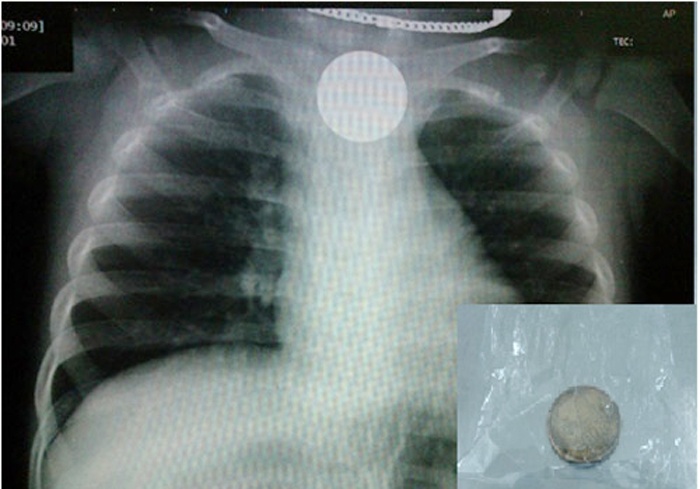

| Tấm phim chụp X-Quang cho thấy đồng xu rơi xuống thực quản của trẻ. Ảnh minh họa. |